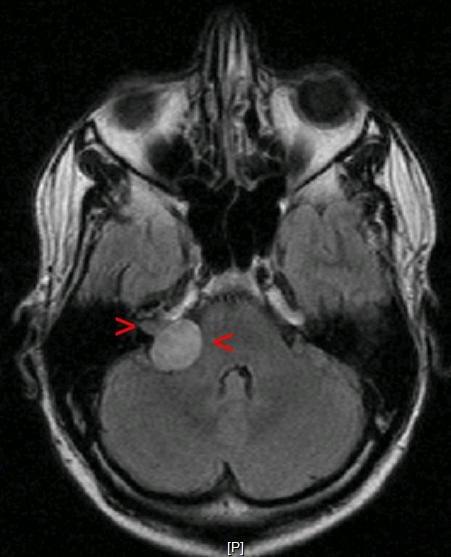

Radiosurgery Dose Reduction for Brain Metastases on Immunotherapy (RADREMI)

Phase I multicenter study assessing the safety and efficacy of dose-reduced stereotactic radiosurgery with concomitant immunotherapy in treating cancer that has spread to the brain

(ClinicalTrials.gov# NCT04047602)